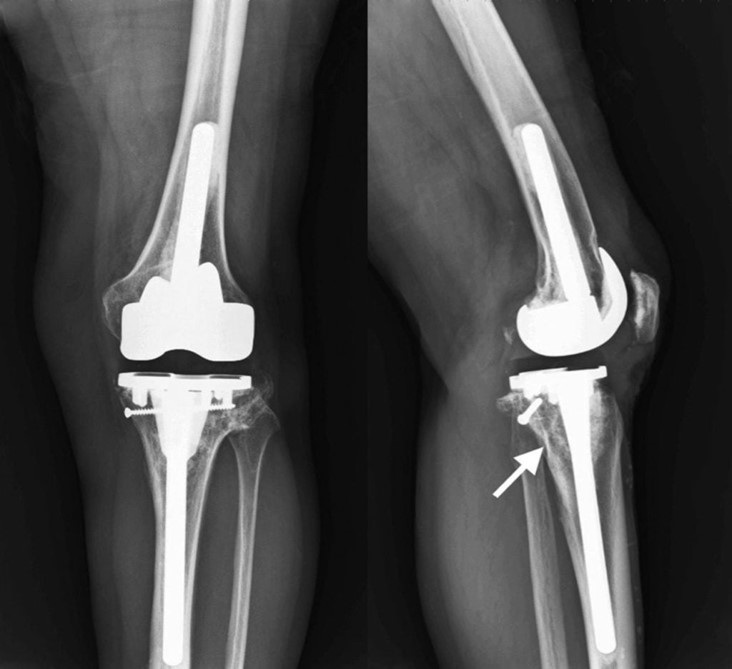

Проектування та виготовлення індивідуальних аугментів для заміщення  дефектів суглобів: М, 48р, асептична нестабільність онкологічного ендопротеза . Заміщення дефекту індивідуальним аугментом та ревізійним ендопротезом , фіксація БІС, ПММА